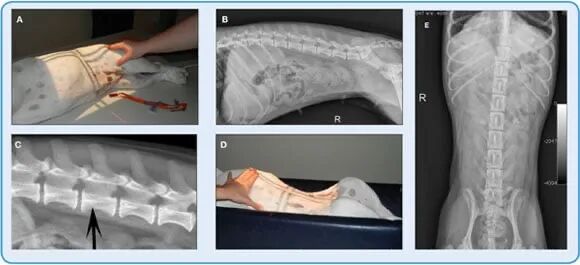

图4.一只大犬的腹背x光照片。一只大犬的头侧(A)和尾部(B)腹背(VD)x线照片;注意两幅图像之间的结构重叠(VD头部图像的尾部和VD尾部图像的头部)。还要注意胸椎和腰椎尾部的直线位置,导致每张图像的左右两侧腹部大小相等。